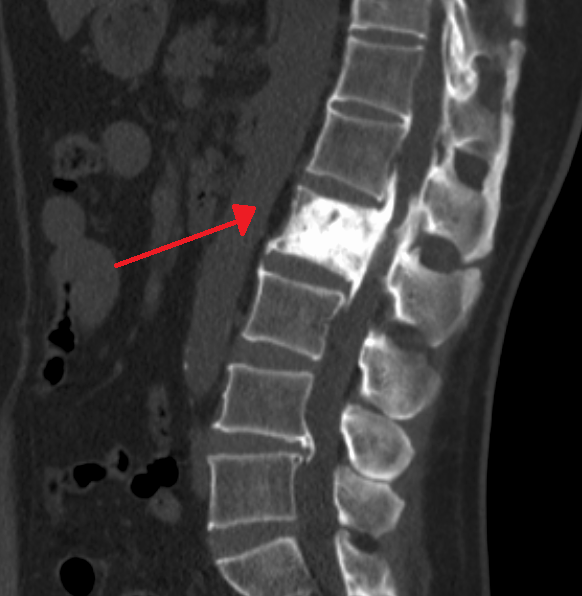

Paget Disease of the Bone

Paget disease of the bone is due to the imbalance between osteoclast and osteoblast function.

Paget disease of the bone often manifests in late adulthood with an average age of more than 60-years-old.

One or more bones are involved in a localized process that does not affect the entire skeleton.

The end consequence of Paget disease of the bone is bone that is dense, sclerotic, and brittle.

Histology of Paget disease of the bone reveals a mosaic pattern of lamellar bone.

Clinical signs of Paget disease of the bone include:

- Hearing loss

- Enlarging head size (having to obtain bigger hats)

- Bone pain

- Microfractures

Patients older than 40-years-old are more likely to have isolated increased alkaline phosphatase, which is the most prevalent cause of isolated raised alkaline phosphatase.

Patients with Paget disease of the bone also tend to have lion-like facies with involvement of the craniofacial bones.